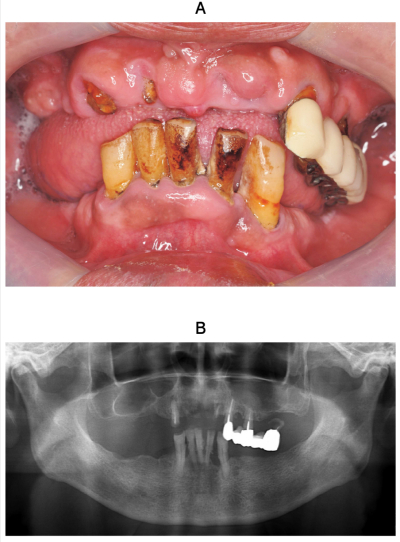

92歳の男性。咀嚼困難を主訴として来院した。3年前に脳梗塞の既往がある。 上顎右側側切歯、上顎左側側切歯および第二大臼歯は保存不可能のため抜去し、下顎には両側犬歯を支台歯とする部分床義歯を製作することとした。初診時の口腔内写真、エックス線写真及び上顎の補綴治療計画の模式図を別に示す。

上顎の治療方針で適切なのはどれか。1つ選べ。